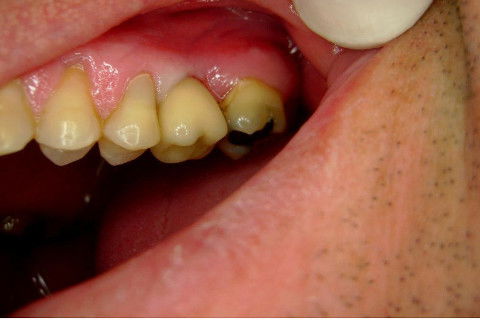

Instalação de um implante em região do 26. Utilizamos um implante cone morse Alvim Neodent 4.3 X 11,5. Foi uma cirurgia muito rápída e minimamente traumática, sem retalho e sutura.